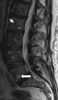

Lytic vertebral lesion

A compression fracture is a collapse of a vertebra. It may be due to trauma or due to a weakening of the vertebra (compare with burst fracture). [Source: Wikipedia ]